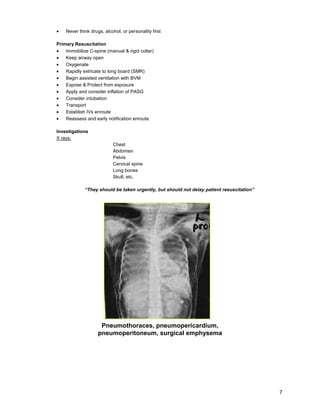

Investigations

X rays:

Chest

Abdomen

Pelvis

Cervical spine

Long bones

Skull, etc.

“They should be taken urgently, but should not delay patient resuscitation”

Pneumothoraces, pneumopericardium,

pneumoperitoneum, surgical emphysema